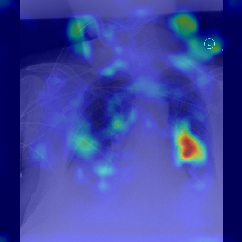

Fig.Β 5: Examples of class activation maps of positive cases. Left to right: image with annotation in blue, no L1 regularization, with L1 regularization, baseline.

Fig. 5 shows examples of class activation maps of positive cases for visual comparisons among the final models. These were produced using the Grad-CAM approach [14]. The images were annotated by an expert for the regions of opacity. Although all models correctly classified the cases as positives, the activation maps of the baseline model were barely correlated with the annotated regions, with more irrelevant hot spots outside the lungs. On the other hand, the activation maps of the models with feature selections were better correlated with the annotation. In other words, these smaller networks seems to be also more focused on the correct regions, which is a step towards explainability. The image in the third row shows that the VGG16 activation map has important components outside the lungs, focusing on English characters on the image. Whereas the reduced networks show more activation in marked areas of the lungs.